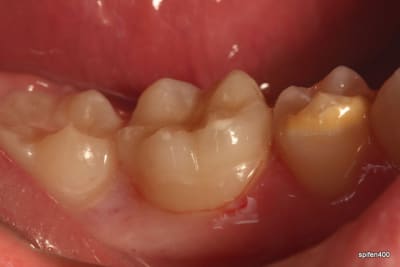

31/10/2011 à 18h09

tiens je me suis chronométré :)

28min :) lol

bon celui la etait un peu long, car provisoire collé au cvi cause durée avec le provisoire trop longue....

donc dur a déposer et obligé d'enlever les résidu de cvi aux US...

ceux qui font pas d'onlay vous proposez quoi là ?

patiente de 13 ans ...

heu spifen 400 c'est pas de la pub lol

Ca ressemble à un beau MIH avec un confrère qui a fait des trucs bizarres avec un amalgame.

Oui MIH déjà avec une belle récidive de carie. Je pense que dans un cas comme ça le compo est voué très vite à l’Échec...